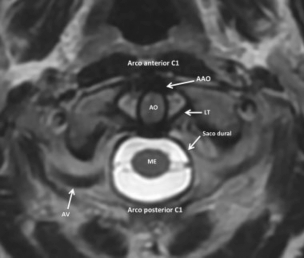

Los ligamentos se visualizan como estructuras de baja señal, o hipointensas, en secuencias potenciadas en T2/DP y cada uno de ellos se analizan en un plano del espacio diferente.13,14,15 Por ejemplo el LT se visualiza mejor en el plano axial, el LA en el plano coronal mientras que el LAp y MT se observan en el plano sagital (►Fig. 11).

RM, corte axial, secuencia CUBE 3D (GE, Healthcare) de la UCC. Se muestra en el corte axial la AAO con la disposición del LT. Abreviaciones: AO, apófisis odontoidea; AV, arteria vertebral; ME, médula espinal.